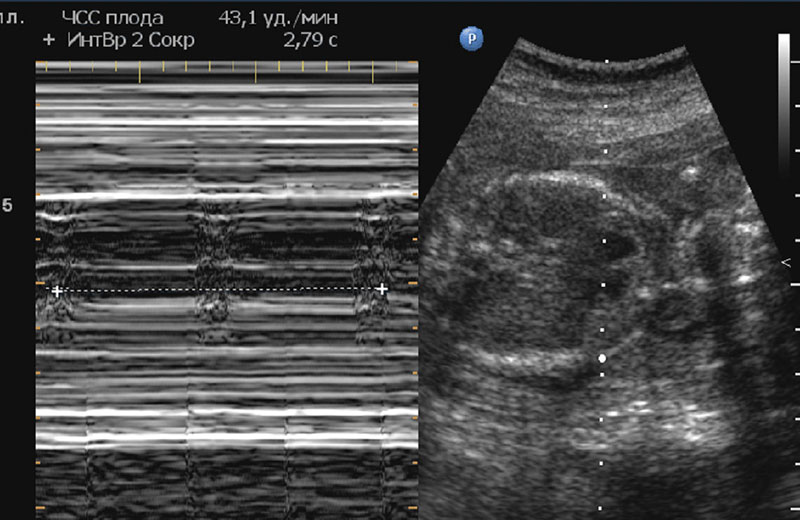

Раннее выявление заболеваний позволяет эффективно контролировать их и снижать вероятность осложнений. Без необходимого лечения шансы на выживание у детей с сердечными патологиями крайне низки. Обычно диагностика кардиопатий у подростков не вызывает затруднений. Однако выявить нарушения в развитии желудочков у новорожденных бывает значительно сложнее. В домашних условиях заметить сбои в работе сердца практически невозможно. Чаще всего кардиопатии диагностируются уже в роддоме, что связано с травмами, асфиксией или инфекциями. Основной причиной отклонений в развитии сердца у младенцев является гипоксия. Длительный недостаток кислорода негативно сказывается на всем организме, включая сердечную мышцу.

При наличии подозрений на кардиомиопатию врач назначает дополнительные исследования и консультацию кардиолога. Для постановки диагноза необходимо провести полное обследование сердца. Это включает создание 3D-изображения органа, регистрацию его функциональных показателей (пульс, давление, наличие шумов) и проверку проводимости тканей. Обычно пациенту назначают:

- эхокардиографию;